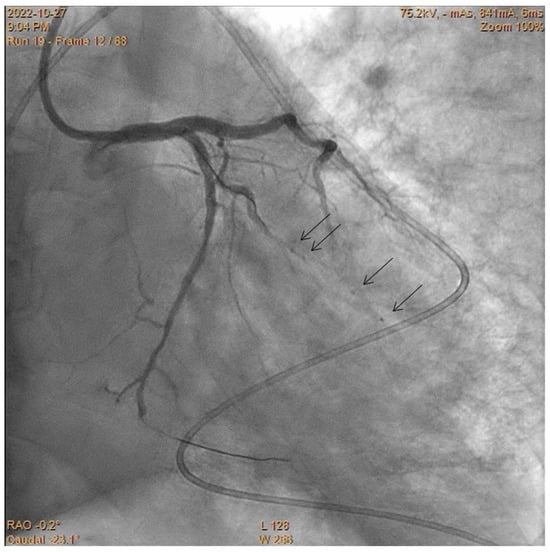

Embolization of Perforated Coronary Artery with a Fragment of Balloon Catheter (Cut Balloon Technique)—Multicenter Study

- Sobieszek, G.; Zięba, B. Balloon Fragment Technique Used to Close Distal Coronary Vessel Perforation. J. Invasive Cardiol. 2020, 32, E370–E372. [Google Scholar] [PubMed]

- Öcal, L.; Yılmaz, C.; Uysal, S.; Cerşit, S.; Zehir, R. Successful management of distal coronary artery perforation with the modified cut balloon technique during percutaneous coronary intervention. Anatol. J. Cardiol. 2022, 26, 66–68. [Google Scholar] [CrossRef] [PubMed]

- Alavi, S.H.; Hassanzadeh, M.; Dehghani, P.; Mehdipour Namdar, Z.; Aslani, A. A Novel Technique for Managing Guidewire-Induced Distal Coronary Perforation Using Coronary Balloon Pieces. JACC Case Rep. 2022, 4, 137–141. [Google Scholar] [CrossRef] [PubMed]

- Abdalwahab, A.; McQuillan, C.; Farag, M.; Egred, M. Novel economic treatment for coronary wire perforation: A case report. World J. Cardiol. 2021, 13, 177–182. [Google Scholar] [CrossRef] [PubMed]